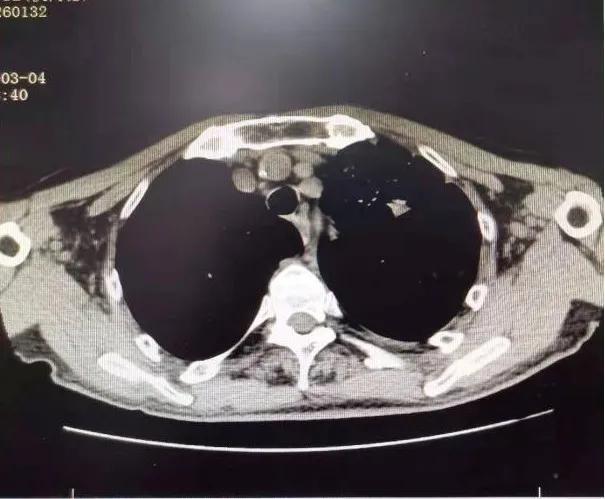

75岁的张爷爷患有慢性阻塞性肺疾病、脑栓塞等多种慢性病,体质较差,PS评分为3分,入院时有咳嗽咯血伴有气短乏力等症状,查胸部CT可见左上肺叶大小约8×4cm大小占位病变,纵隔淋巴结肿大,左侧大量胸腔积液。 气管镜可见左上支气管内新生物阻塞。 病理提示: 鳞状细胞癌。 诊断为: 肺癌(左肺 鳞癌 cT4N2M1a,IVA期)。 确诊后家属考虑患者年老体弱,合并多种疾病,拒绝放化疗,准备放弃治疗。

1个月后张爷爷来院复诊,复查胸部CT提示:左肺上叶肿块缩小到1cm,肺不张明显缓解,胸腔积液减少 。 张爷爷表示近1月来态势明显好转,未再咯血,活动也不像之前那样一动就喘,平时走路吃饭都不影响。入院后PS评分1分,临床疗效评估为PR。 为更好的控制肿瘤,进行了第二次介入治疗。 行支气管动脉及胸廓内动脉造影后显示肿瘤染色明显减少,继续灌注化疗药物后,将肿瘤滋养动脉进行了彻底栓塞。 术后无不适, 顺利完成第二次治疗。